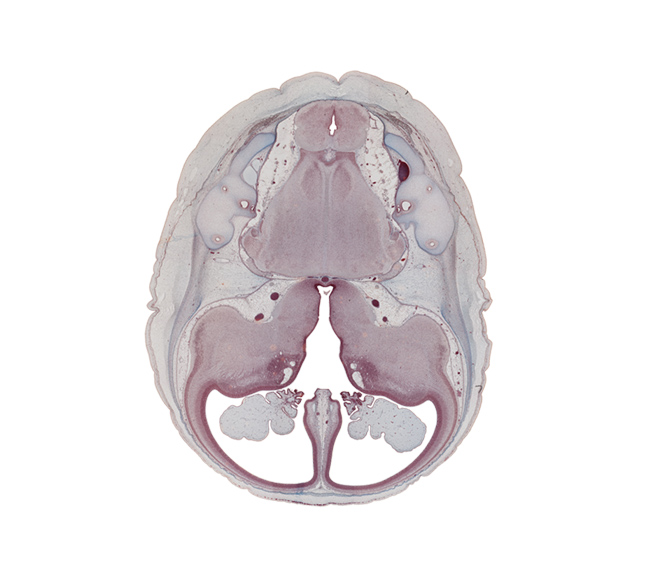

Keywords: anterior inferior cerebellar artery, anterior semicircular duct, basilar artery, common limb of semicircular duct, cortical plate, decussation, endolymphatic duct, falx cerebri region, insula of cerebral hemisphere, internal carotid artery, lateral ventricle, lateral ventricular eminence (telencephalon), medial ventricular eminence (diencephalon), nucleus cuneatus, nucleus gracilis, nucleus of spinal tract of trigeminal nerve, oculomotor nerve (CN III), optic tract, pons region (metencephalon), posterior inferior cerebellar artery, posterior semicircular duct, pyramidal tract region, root of cranial accessory nerve (CN XI), root of glossopharyngeal nerve (CN IX), root of vagus nerve (CN X), subarachnoid space, third ventricle, trochlear nerve (CN IV)

Source: The Virtual Human Embryo.